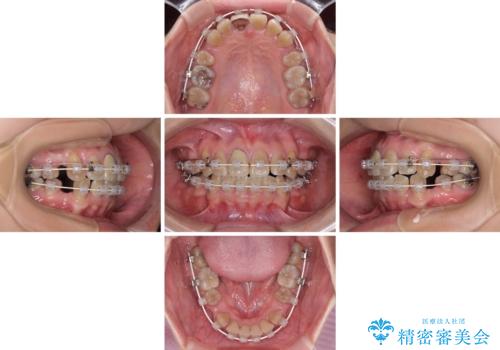

八重歯とクロスバイト 目立たないワイヤー装置での抜歯矯正

歯列が前方に傾斜しており、デコボコが強かったため、上下左右第一小臼歯4歯を抜去し、ワイヤー装置による矯正治療を行うこととしました。

上下の正中がずれていましたが、抜歯矯正であったので、極力正中位置を合わせるように治療を進めて行きました。

顎間ゴムの使用などにより、正中位置を改善することができました。